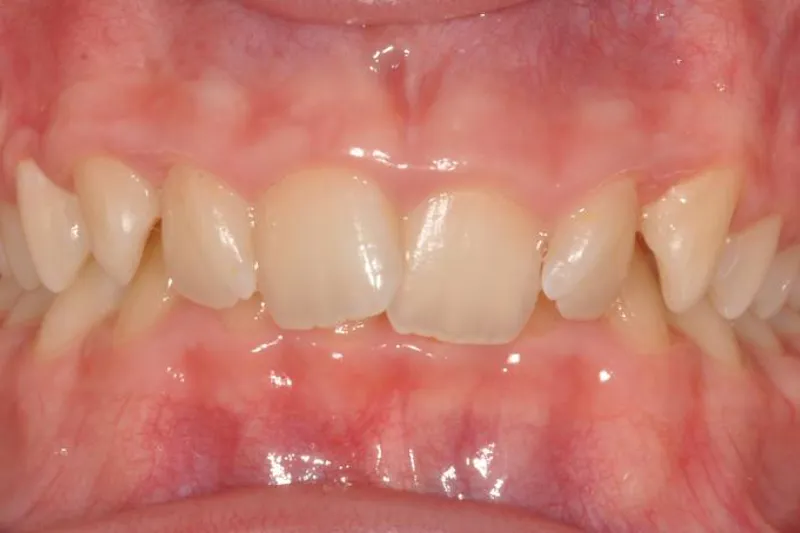

Mindst et af følgende kliniske tegn skal være til stede for at stille diagnosen dybt bid:

- gingival påbidning

- overkæbeincisiverne overlapper > 2/3 af underkæbeincisiverne

- vertikalt overbid på > 4 mm

Betegnelsen dækbid bliver undertiden brugt, når overkæbetænder i fronten bider helt forbi underkæbetænderne. I ekstreme tilfælde kan overbiddet være så stort, at overkæbeincisiverne har kontakt med slimhinden facialt for underkæbeincisiverne.